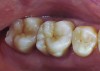

Figure 9 Preoperative preparation with composite block-out restoration, final cementation of Class IIb material, and final ceramic contour and stain by Steve Lee, CDT, MDC.

Figure 9

Figure 10 Preoperative preparation with composite block-out restoration, final cementation of Class IIb material, and final ceramic contour and stain by Steve Lee, CDT, MDC.

Figure 10

Figure 11 Preoperative preparation with composite block-out restoration, final cementation of Class IIb material, and final ceramic contour and stain by Steve Lee, CDT, MDC.

Figure 11